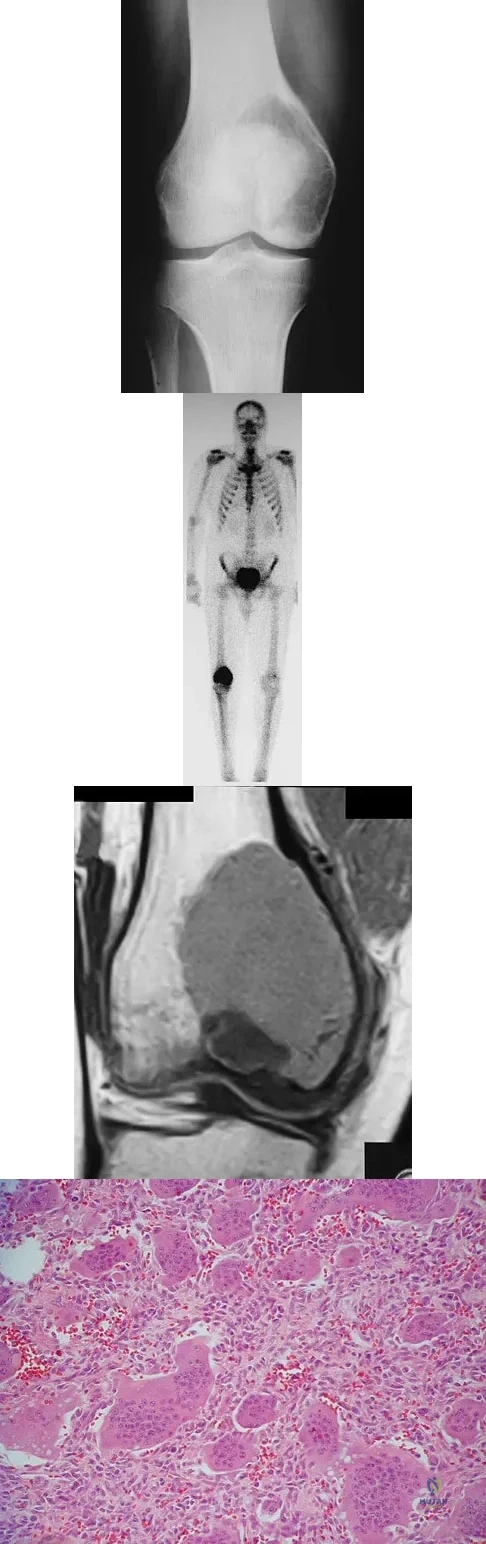

Question 16

A 35-year-old man has had progressive right knee pain for the past 2 months. An AP radiograph, bone scan, MRI scan, and photomicrograph are shown in Figures 34a through 34d. What is the most appropriate treatment of this lesion?

Question 18

A 30-year-old woman has had pain in her right leg for the past 6 months. A lytic lesion is noted in the anterior cortex of the midtibia, extending 5 cm in length without a soft-tissue mass. A radiograph and a biopsy specimen are shown in Figures 35a and 35b. What is the preferred treatment?

A 75-year-old woman has had severe shoulder pain for the past month. Her medical history includes hypertension and a total nephrectomy for renal cell carcinoma 7 years ago. Radiographs and sagittal MRI scans are shown in Figures 36a through 36d. A bone scan reveals this to be an isolated lesion. Biopsy findings are consistent with metastatic renal cell carcinoma. What is the most appropriate treatment for this patient?

Explanation

A 14-year-old girl has had progressive heel pain for the past several months. Based on the radiograph, MRI scan, and biopsy specimens shown in Figures 37a through 37d, treatment should include

Explanation